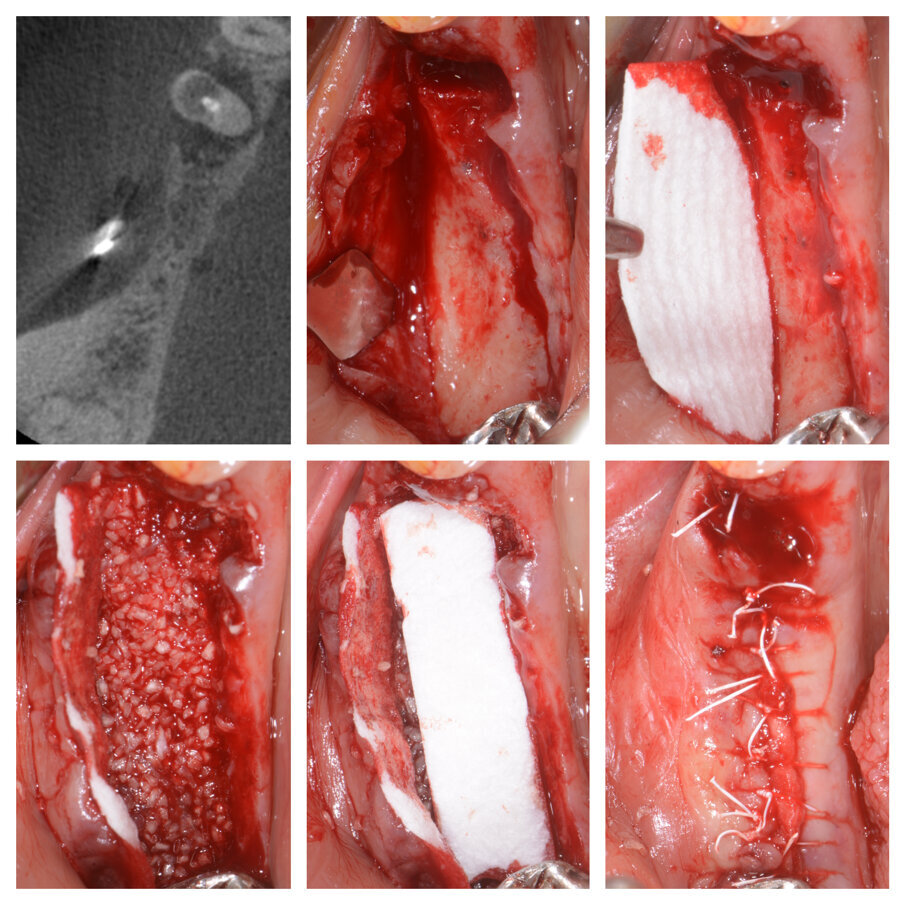

Fig. 6a_Perdita di elemento di ponte 24 e deficit in zona 25, fasi chirurgiche e guarigione.

Fig. 6b_Rientro chirurgico per il posizionamento implantare e protesi definitiva.

Fig. 6c_Controllo rx a 2 anni dal posizionamento implantare.